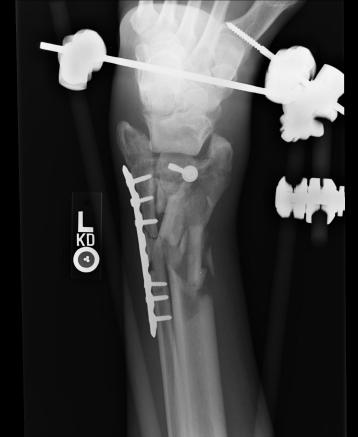

Pre-skin graft & bone infuse surgery X-Rays of the left ankle

These x-rays were taken just prior to surgery where grafts of skin (from Liam's own leg) were used to cover the open wound on Liam's left

ankle. Dr. Gottlieb also took the initiative to infuse material into the tibia gaps (shown in the front ankle view). The infused bone material

should fill in the existing bone gaps and fuse the various bone fragments, resulting in a much stronger support structure. It is hoped that the

3 cm fragment (shown in the side view) will fuse with the other tibia bones as time progresses. No immediate plan exist to modify the remaining

bone fragments / configuration.